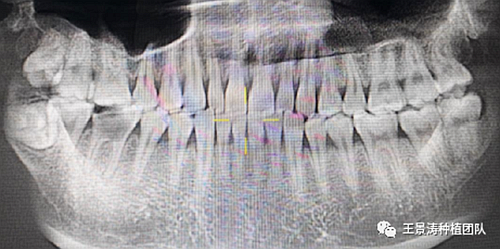

下述病例則是15區(qū)域的即刻種植,15因牙冠折斷于齦下,無法樁核冠修復(fù),則考慮種植修復(fù)。但拍攝CBCT后發(fā)現(xiàn)根尖距上頜竇底距離較短?;颊邽槟贻p女性,無全身系統(tǒng)疾病且可利用上頜竇底與根尖皮質(zhì)骨雙側(cè)皮質(zhì)骨固位,且此位置可通過頰側(cè)軟組織減張技術(shù)獲得嚴(yán)密封閉牙槽窩。因其根尖距上頜竇距離較低,遂拔除15后行上頜竇內(nèi)提升,埋入式種植,最終修復(fù)的完成。